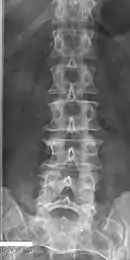

Several congenital block vertebrae in the transition from the thoracic to the lumbar spine and hemivertebrae.

Congenital block vertebra in the lumbar spine (partial vertebrae 3 and 4). The rear portion of the disc still exists.